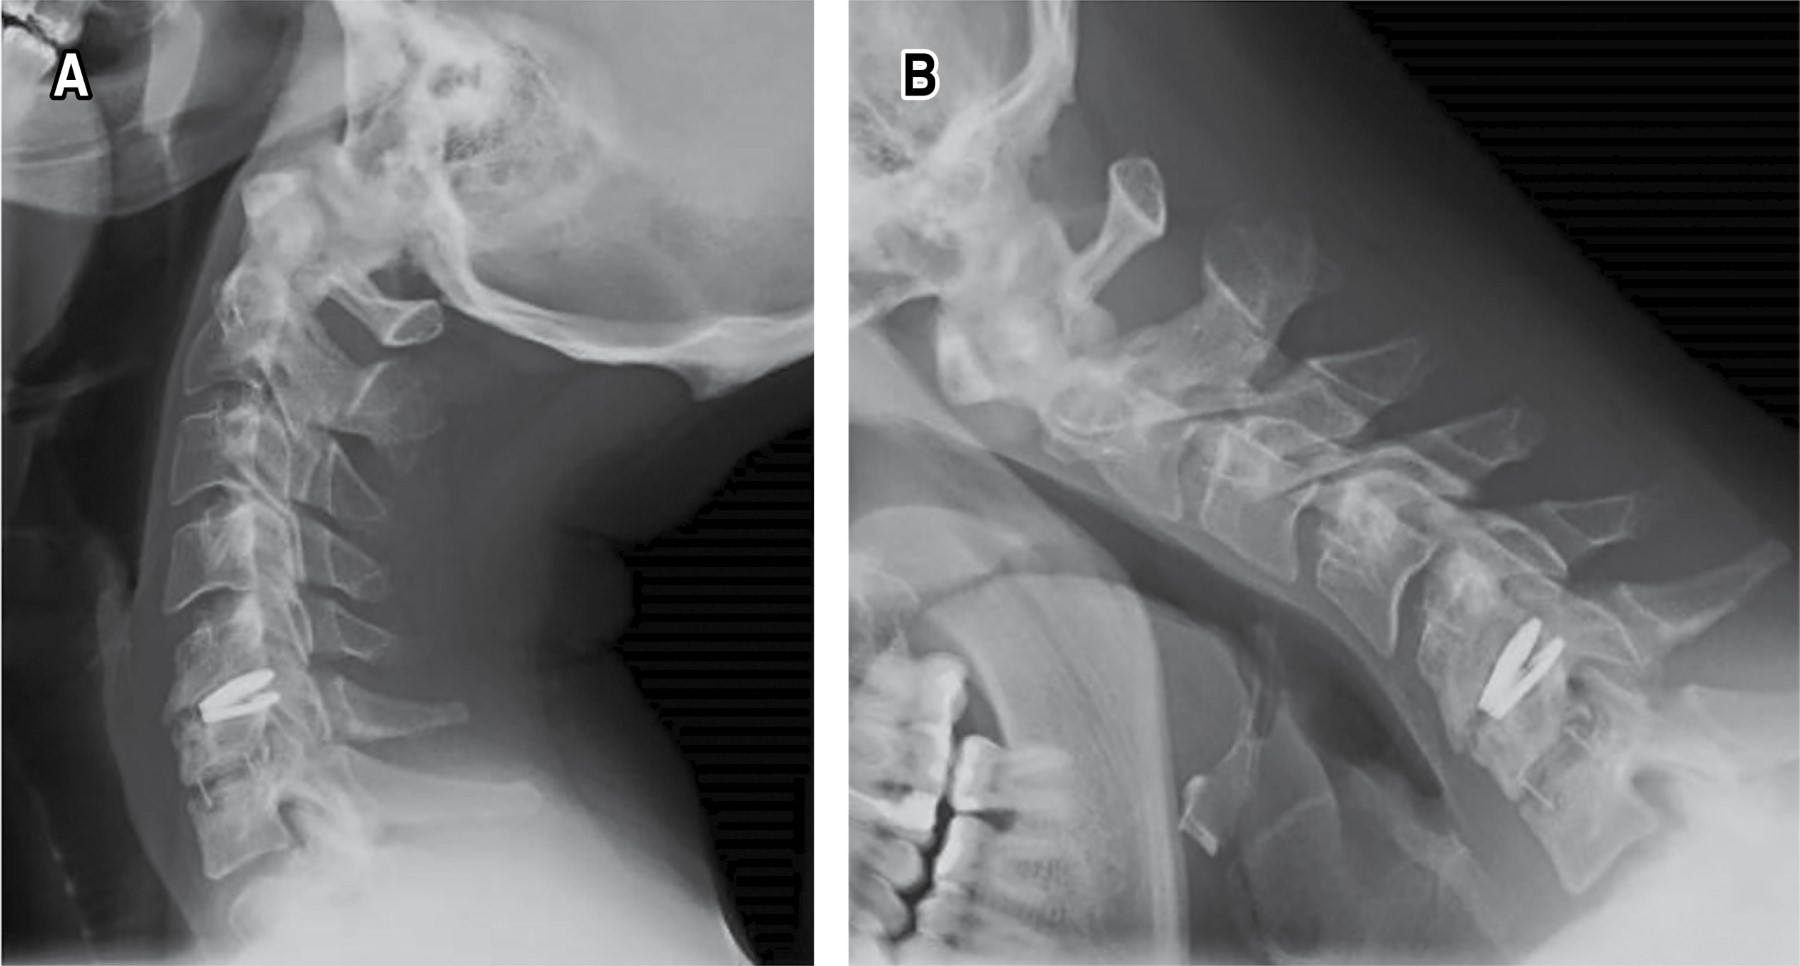

Introduction: cervical disc arthroplasty as a surgical treatment of spondylosis is a technique that has gained popularity in recent years with the advantage of maintaining movement and reducing the development of adjacent segment disease. Despite this, it is not free of complications, one of the least frequent being implant dislocation, with very few official reports in the global literature. A case report of a Baguera C type prosthesis is presented, a bibliographic review is carried out covering the different prosthetic devices that have an official report in the literature, frequencies, associated factors and treatment used are analyzed. Clinical case: 30-year-old male undergoing surgery for long-standing neck pain and myelopathy secondary to C5-C6 disc herniation and C6-C7 spondylosis. Hybrid cervical arthroplasty was performed with placement of a Baguera C disc prosthesis at C5-C6 and a CeSPACE interbody spacer at C6-C7. 13 months later he returned to the clinic with pain and refractory symptoms, X-rays were taken showing posterior dislocation of the implant. Revision surgery was performed, removing the implant, placing an interbody spacer plus bone graft, and placing an anterior locked plate with complete remission of symptoms. Conclusions: prosthetic dislocation is rare, the literature reports few cases, this being the first related to the Baguera C prosthesis, surgical treatment is imperative. The female sex and the C5-C6 level are the most affected, the previous variant is the most common. Careful placement and proper selection of the implant size are the most important factors to take into account and reduce the chances of failure. When it occurs, arthrodesis is usually the most used option with favorable results.

Figure 2